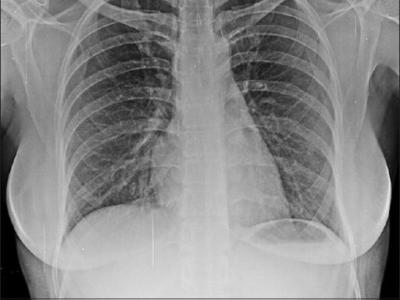

Psoriatic Arthritis at Risk for Interstitial Lung Disease A TriNetX EHR study shows that psoriatic arthritis (PsA), but

Psoriatic Arthritis at Risk for Interstitial Lung Disease A TriNetX EHR study shows that psoriatic arthritis (PsA), but not Psoriasis (PsO), patients are at increased risk for interstitial lung disease (ILD). https://t.co/2zuxF1PY3Q. https://t.co/Icck4qE76X